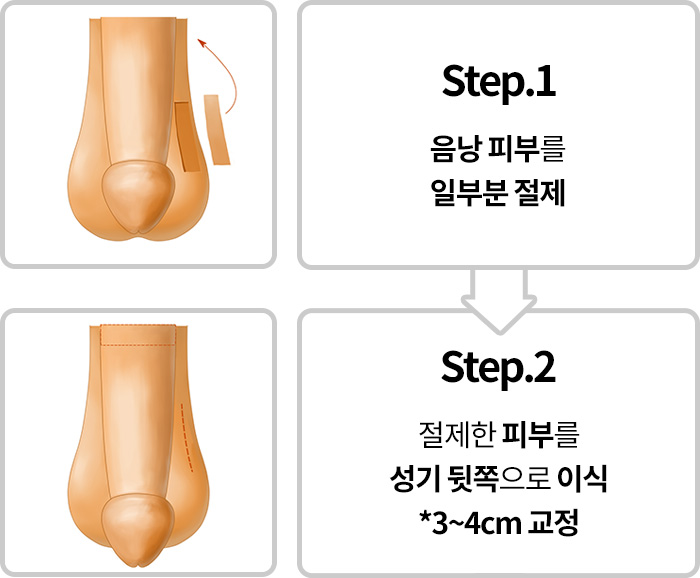

음경피부

포경수술과 같은 남성수술 시

음경피부를

과도하게 제거하는

부작용에 의해 길이가 짧아진 경우